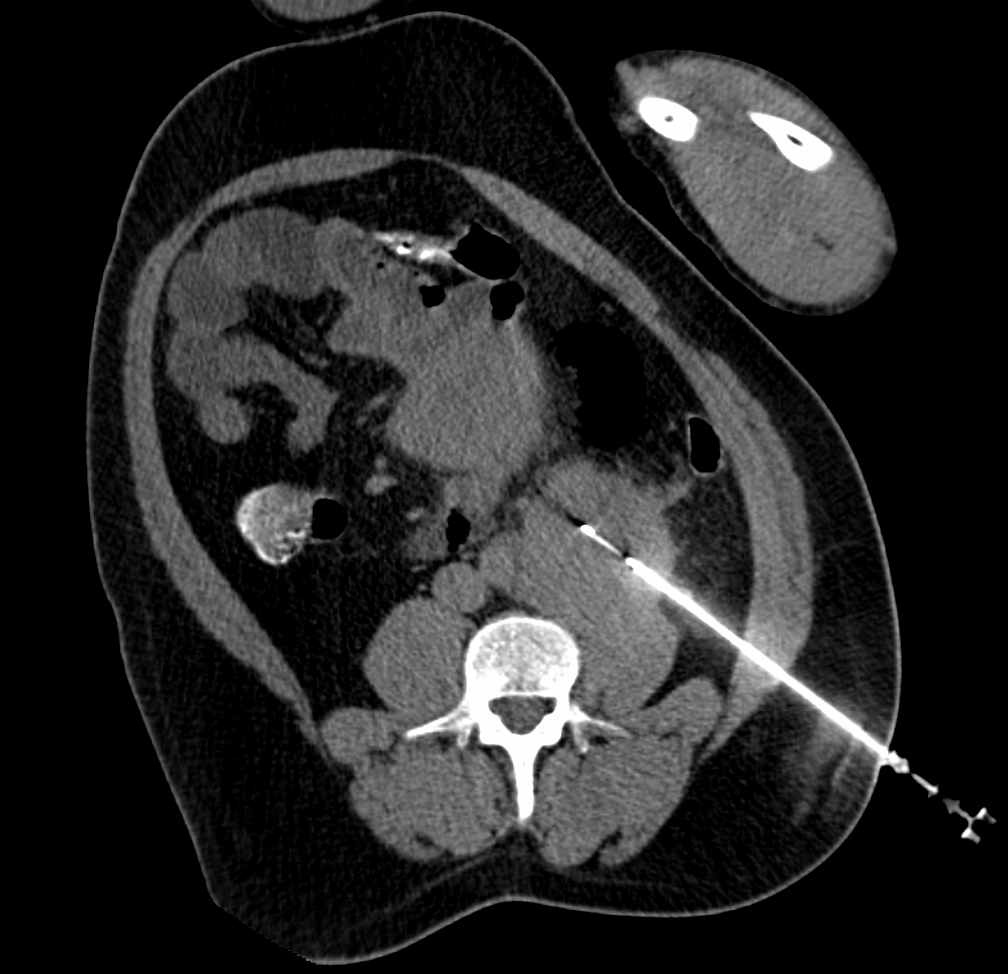

Biopsia guiada por pet-ct